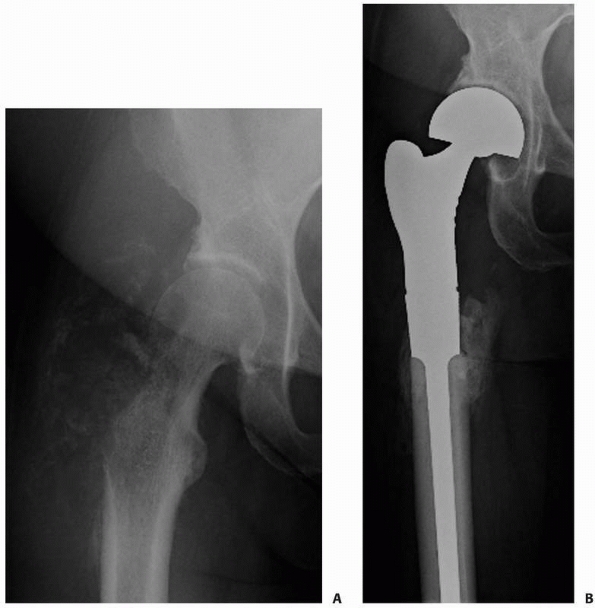

Accordingly, there is a high incidence of failure if traditional

fracture fixation devices are used. The procedure of choice for

patients with metastatic disease to the femoral head or neck is a

cemented replacement prosthesis56,71 (Fig. 20-9).

FIGURE 20-9 A.

Anteroposterior radiograph of the left hip in a 52-year-old woman with metastatic lung carcinoma. There is an impending fracture caused by an osteolytic lesion in the medial aspect of the femoral neck. B. Postoperative radiograph after placement of a cemented medium-length, calcar-replacing, bipolar hemiarthroplasty. |